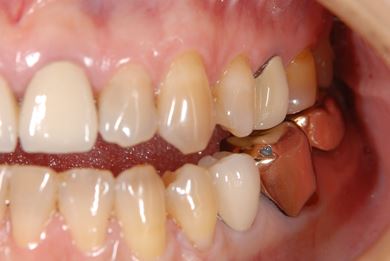

治療前

• 治療前